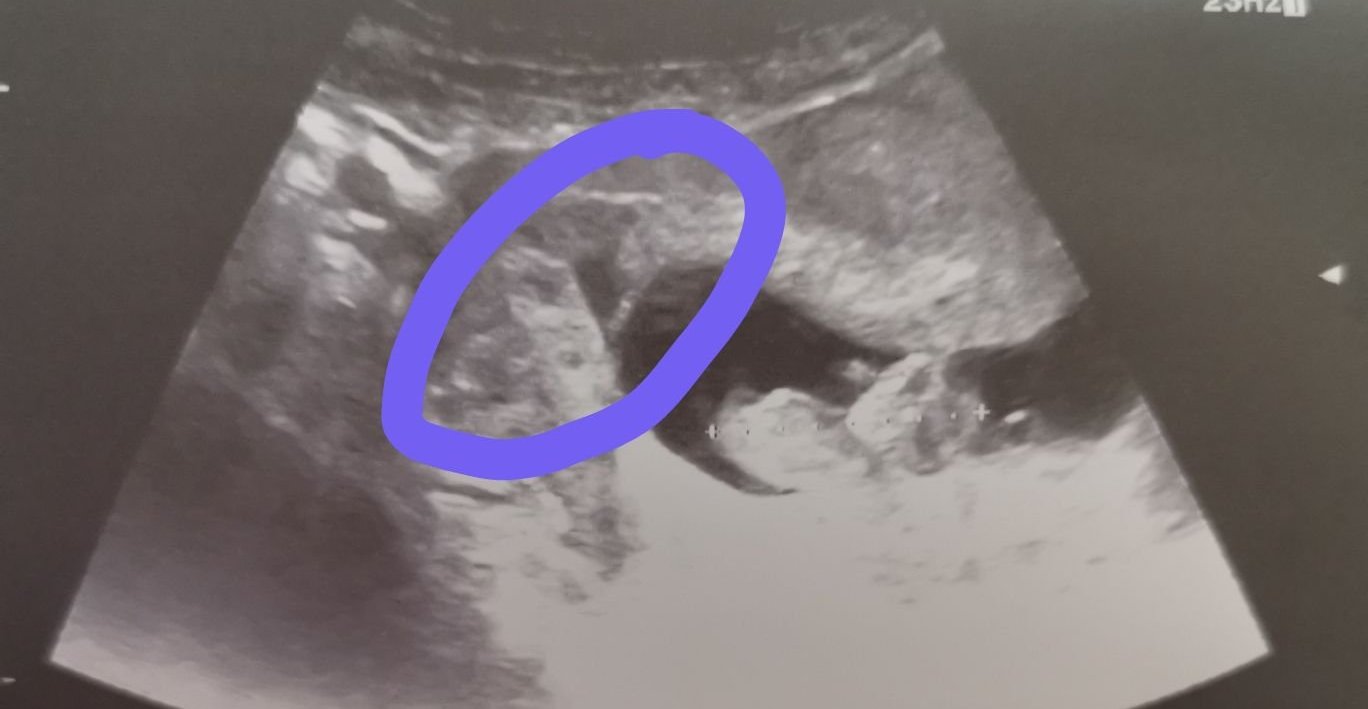

Уф, аз сега четох листовката за този Дуфастон. Голяма отрова, защо ли я четох. Ама след като док преценя, че трябва, ще го пия. Дано е само две седмици. Момичетата, които имаха леко отлепянето, какво пиха и колко време, и дали помагат медикаментите? Това в кръгчето е при мен, което отчете,но каза че още не е притеснително.